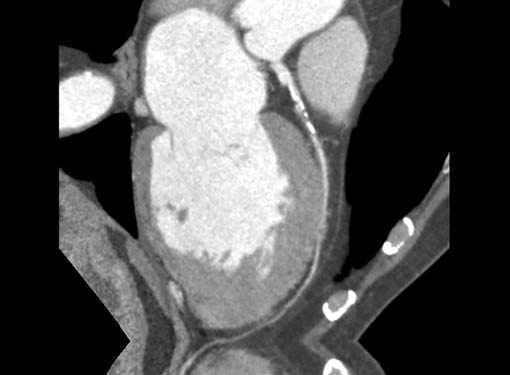

Pulmonary thromboembolism can be a presenting feature

in renal cell carcinoma, bronchial carcinoma. Rarely HIV

(Fig. 15) can present initially with pulmonary throm boembolism

in which case they can be either bland or septic.

Filling defects (Figs 16A and B) may be seen in main

pulmonary artery (MPA), left pulmonary artery (LPA) and

right pulmonary artery (RPA), interlobar artery, segmental

divisions (Figs 17A and B). On occasions, detection in distal